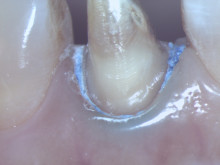

赤い丸の部分にマイクロスコープで見ると根管の入り口が確認できます。

ここは肉眼では確認することができずに、治療されていませんでした。 |